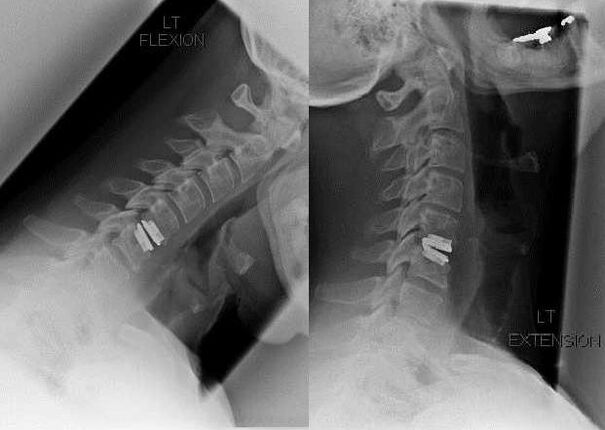

Les indications d'une intervention chirurgicale incluent l'inefficacité du traitement conservateur, ainsi que les complications de l'ostéochondrose cervicale, par exemple la myélopathie discogène, le syndrome de l'artère vertébrale et le syndrome radiculaire. Pour décompresser la moelle épinière, les vaisseaux sanguins et les racines vertébrales, les opérations suivantes sont effectuées :

- laminectomie;

- laminotomie;

- foraminotomie;

- facetectomie;

- discectomie.

Au cours de l'intervention chirurgicale, des fragments osseux et des ligaments peuvent être excisés et les disques intervertébraux peuvent être complètement ou partiellement retirés. Pour les petites saillies herniaires, une vaporisation laser du noyau du disque est souvent réalisée.

Après l'excision des structures vertébrales, la stabilisation des segments de mouvement de la colonne vertébrale est souvent nécessaire par fusion vertébrale ou par la pose d'autogreffes osseuses et cutanées.